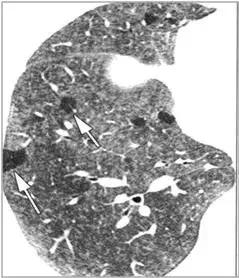

CT征象七:马赛克灌注

马赛克灌注(Mosaicperfusion)

在HRCT上,由于气道疾病或肺血管性疾病引起相邻的肺区血液灌注上的差别而出现的不均匀肺密度区,称马赛克/镶嵌性灌注。常见于造成局部气体滞留或肺实质通气不良疾病中 。

HRCT示略高密度磨玻璃密度影和低密度马赛克灌注区

由于气体储留引起的马赛克灌注

小气道病变引起两侧肺的马赛克灌注

小气道病变引起两侧肺的气体潴留